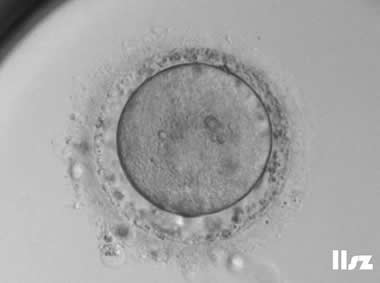

3. 成熟卵母细胞(MII)及其COCs(正常COCs)

卵细胞呈现规则的圆形且颜色较浅,放射冠完全分散,颗粒细胞团较大,排列稀疏。成熟卵母细胞一般在取卵后体外培养2-6小时再行授精。

|  |

| 0小时COCs的MII卵(4x) | 0小时COCs的MII卵(10x) |

|  |

| 2小时COCs的MII卵(10x) | 4小时去颗粒细胞后的MII卵(10x) |